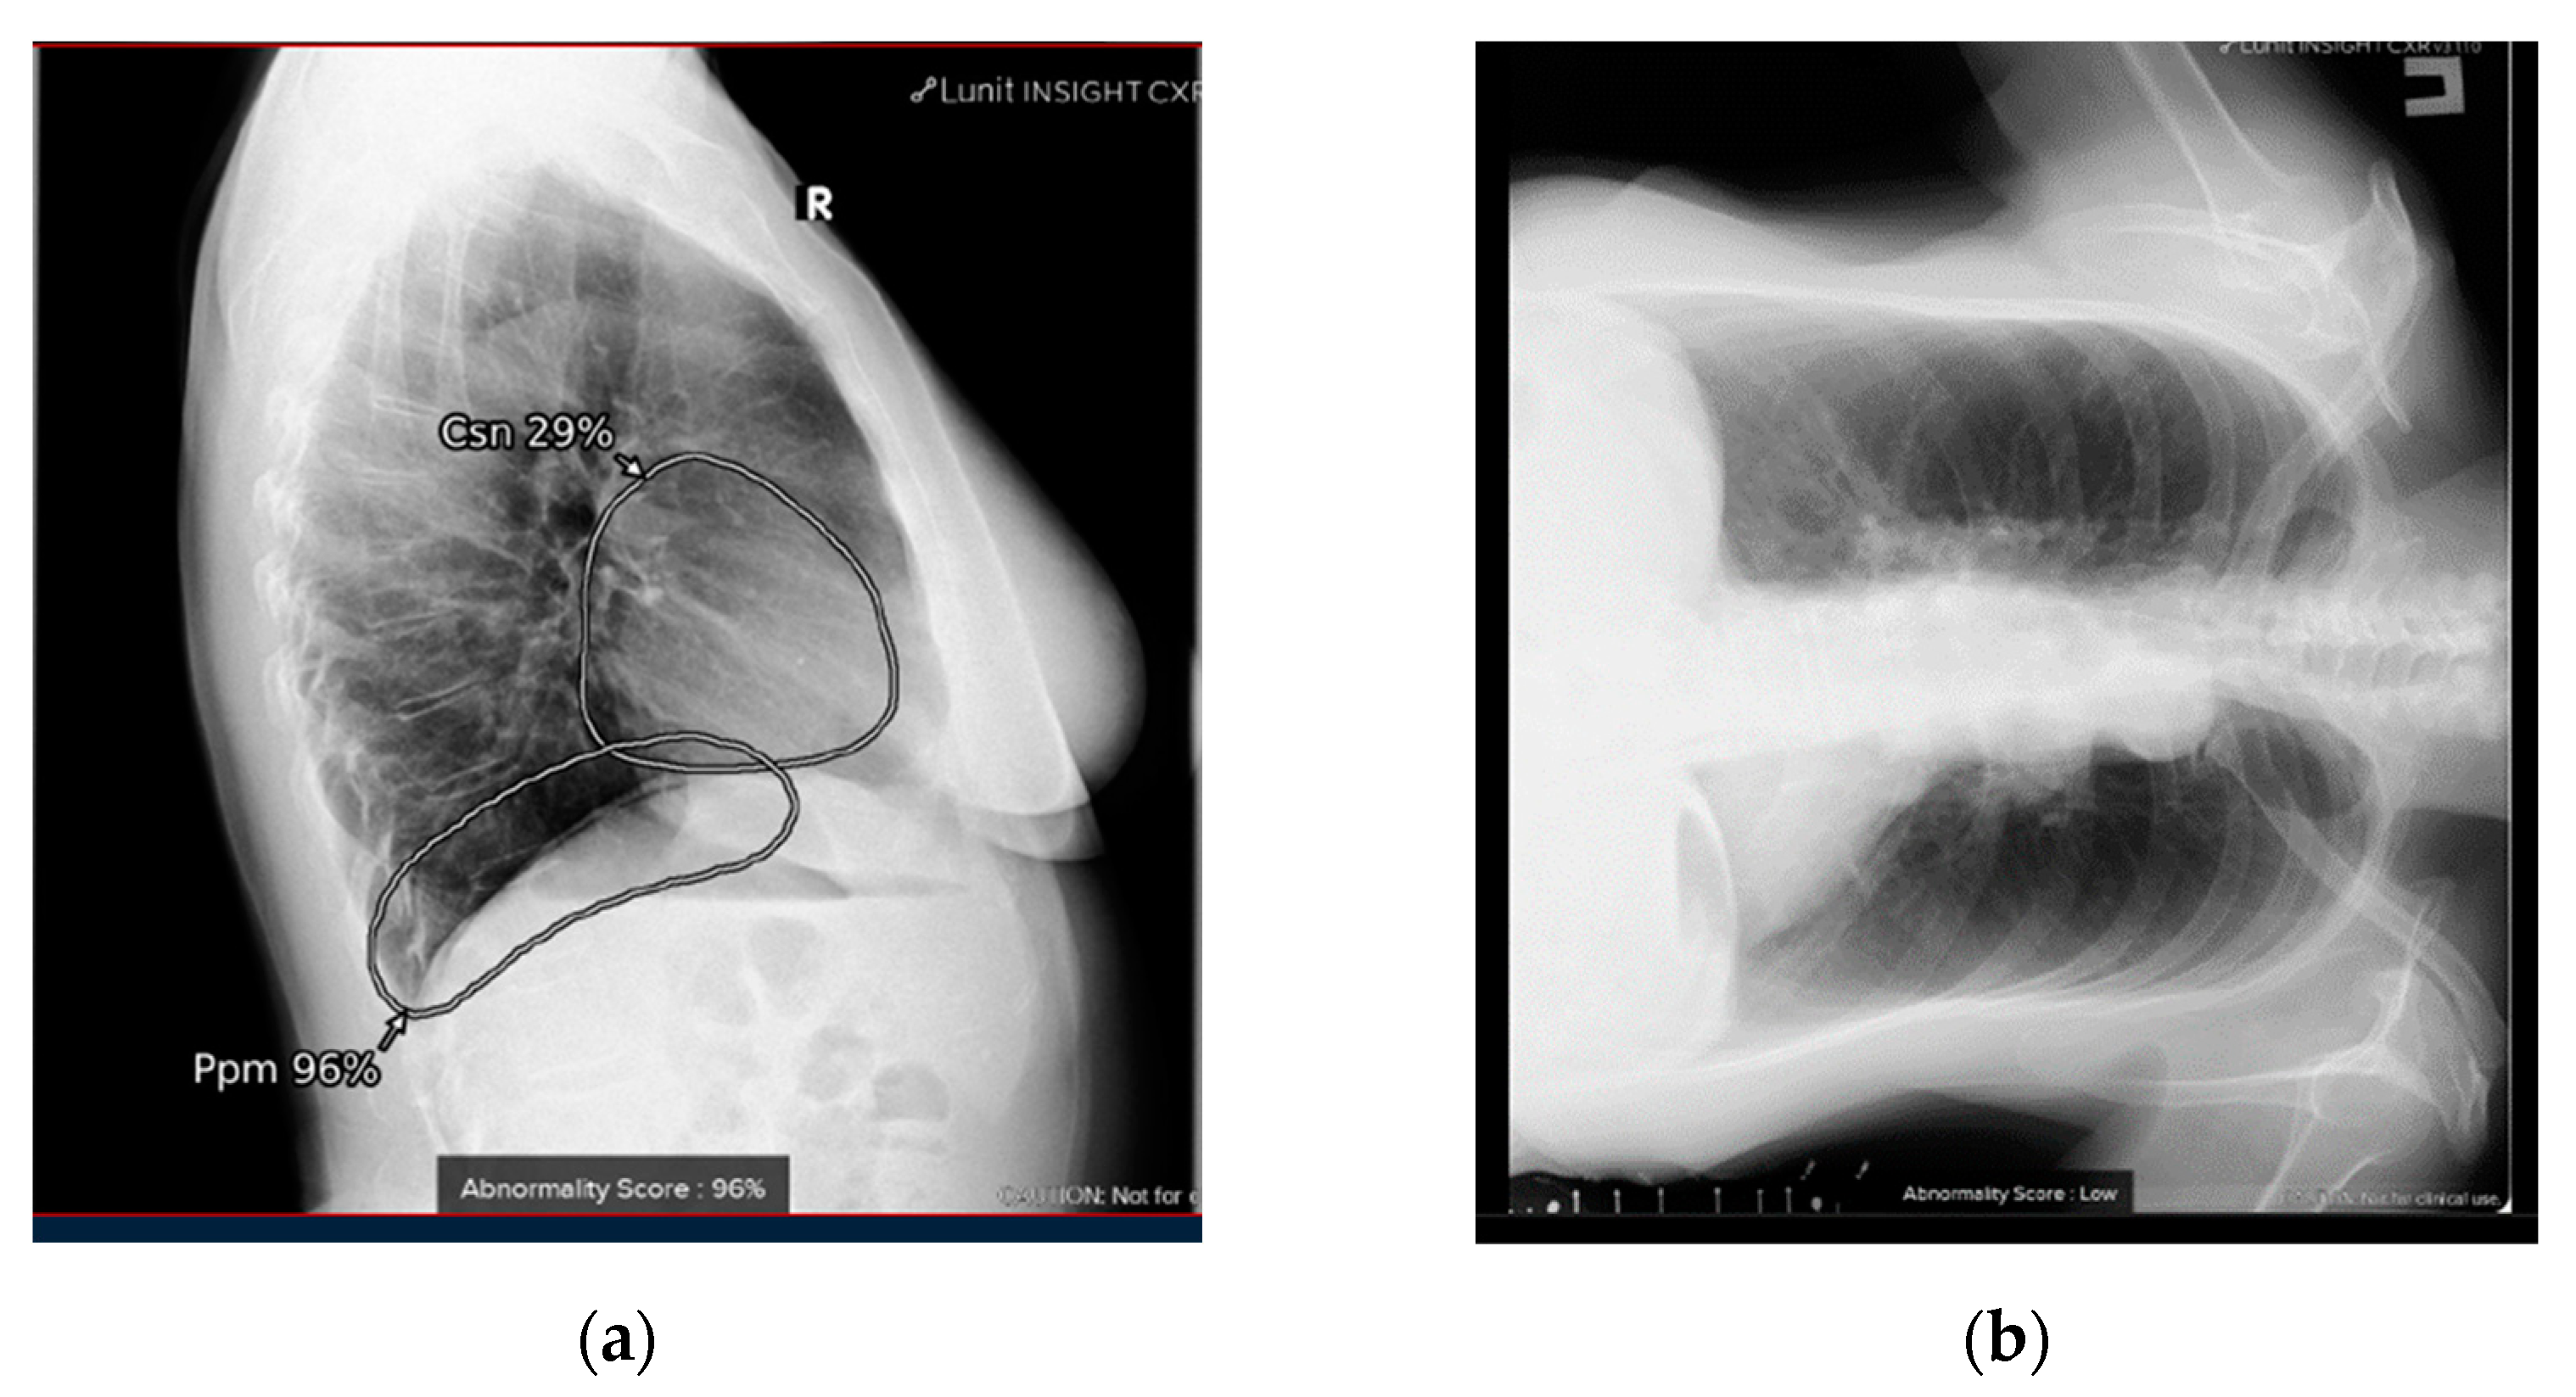

4.1. Additional Data and Technical Assessment of the Quality of Input CXR